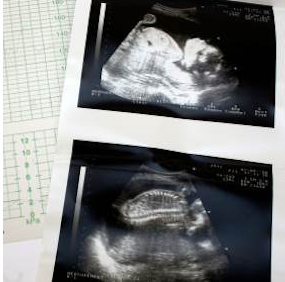

Hút thuốc lá khi mang thai hết sức nguy hiểm vì đặt cả bạn và con của bạn vào những rủi ro. Trong thuốc lá có chứa các chất hóa học độc hại, bao gồm nicotin, cacbon monooxit, và hắc ín. Khói thuốc làm gia tăng đáng kể các biến chứng trong thai kì, bao gồm cả tử vong mẹ và thai nhi.

Ra máu âm đạo bất thường là một dấu hiệu đáng báo động dù ở giai đoạn nào của thai kì. Sảy thai thường xảy ra vào 3 tháng đầu của thai kì. Tuy hiếm gặp nhưng thai chết lưu cũng có thể xảy ra sau tuần thứ 20. Hút thuốc lá làm tăng tỉ lệ sảy thai cũng như thai chết lưu do những chất hóa học độc hại ẩn chứa trong khói thuốc.

Những vấn đề về rau thai hoặc chậm phát triển trong tử cung cũng là những biến chứng do thuốc lá, có thể gây sảy thai hoặc thai chết lưu.